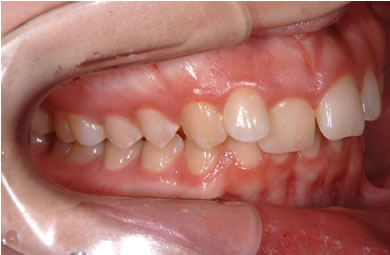

| 性別/年齢 | 女性 / 19歳 | ||||||||||||||||||||||||||||||||

| 主訴 | 上のデコボコの歯を綺麗にしたい。 | ||||||||||||||||||||||||||||||||

| 治療方針 | 上顎の歯の傾斜を正常に治す事で下顎を正常な位置に推進させ、非抜歯にて治療を行う。また、上下の顎のずれの治療のため、装置にゴムを使用し審美的・機能的に良い咬合を獲得させる。 | ||||||||||||||||||||||||||||||||

| 治療内容 | 唇側矯正(シルバー) | ||||||||||||||||||||||||||||||||

| 治療期間 | 1年9ヶ月 |